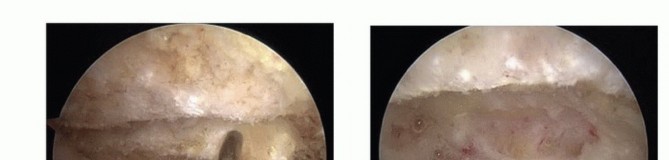

Subacromial Decompression Twenty milliliters of 1% lidocaine and 1:300,000 diluted epinephrine are injected into the subacromial space before intra-articular diagnostic arthroscopy. From the posterior portal, the cannula and trocar are redirected from the intra-articular position to the subacromial space. The correct position is confirmed by palpating the hard undersurface of the acromion with the trocar tip. Once the trocar is felt to be in the subacromial space, it is swept laterally through the subdeltoid bursa to open the subacromial space. Care should be taken to avoid sweeping the trocar medial to the AC joint, which could injure the acromial branch of the thoracoacromial artery. The arthroscope is introduced and an initial assessment of the subacromial bursa and acromial spur is done. A 5-mm skin incision is used to establish the lateral portal 2 to 3 cm distal to the midlateral border of the acromion. A 5.5-mm full-radius resector is introduced through the lateral portal. Visualization is often difficult because of the thickened and inflamed subacromial bursa. Therefore, triangulation of the arthroscope and full-radius resector must be done by palpation. Bursectomy cannot be initiated until the cutting flutes of the resector are visualized. The tip of the anterolateral aspect of the acromion is palpated with the resector to confirm the correct subacromial orientation. Bursal resection is completed in an anterior to posterior and lateral to medial direction(TECH FIG 2A). Care must be taken not to resect the highly vascular bursal tissue medial to the musculotendinous junction of the rotator cuff. A radiofrequency electrocautery device is used to coagulate any bleeding and remove the remaining soft tissue from the undersurface of the acromion, starting at the anterolateral corner of the acromion(TECH FIG 2B).

The electrocautery device is used to peel the coracoacromial ligament from the undersurface of the acromion and completely excise the remaining ligament stump. A complete resection of the coracoacromial ligament is confirmed when the undersurface of the deltoid is visualized as it drapes over the acromial edge(TECH FIG 2C). Anterior acromioplasty is performed with a 5.5-mm burr via the lateral portal. Resection begins in the anterolateral corner of the acromion. The desired depth of resection, estimated from the preoperative films, is obtained by measuring with the diameter of the burr(TECH FIG 2D).

TECH FIG 2 • A. Arthroscopic bursectomy. The bursa overlying the tendinous portion of the rotator cuff must be thoroughly resected to evaluate the tendons for bursal-side rotator cuff tear. B. Soft tissue on the undersurface of the acromion is denuded with a radiofrequency electrocautery. Removing the soft tissue will expose the bony undersurface of the acromion and facilitate acromioplasty by the burr's cutting flutes. C. The acromial spur is now completely visualized. The coracoacromial (CA) ligament must be completely resected from the anterolateral acromion. Failure to do so may result in residual impingement by the CA ligament. Visualization of the undersurface fibers of the deltoid indicates a complete CA ligament resection. D. The acromioplasty begins at the far anterolateral tip of the acromion. The burr's diameter, usually 5 to 6 mm, is used to assess the initial depth of the acromial resection. The acromioplasty proceeds in 5- to 6-mm strips from anterior to posterior and lateral to medial. E. Completed acromioplasty. The undersurface of the acromion is converted to a type I morphology. Any residual ridges or rough edges can be safely smoothed with the burr in the reverse cutting position. F. View of the acromioplasty from the lateral portal. At the procedure's completion, the arthroscope should be placed in the lateral portal to assess the acromion for any residual downslope or unresected bone. The AC joint is also well visualized from this portal and may be resected or coplaned via the anterior portal. G. Coplaning of the AC joint. The posterior or lateral portal is used for arthroscopic visualization. Coplaning is performed with the burr in the anterior or lateral portal. This depth of resection is achieved anteriorly from the anterolateral corner of the acromion to the medial acromial facet of the AC joint. The depth of resection is then progressively thinned posteriorly to the midportion of the acromion such that there is a smooth zone of transition from the anterior to the midportion of the acromion(TECH FIG 2E).